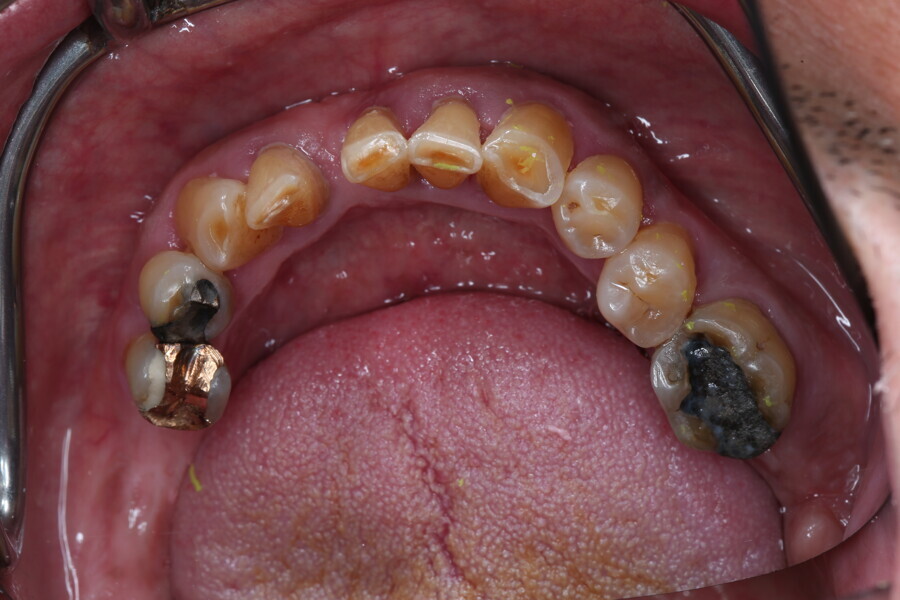

Compromised maxillary dentition treated with Straumann Pro Arch and a digital workflow